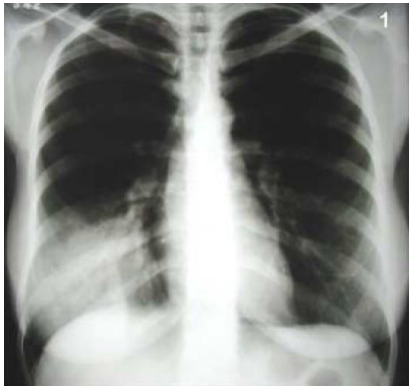

Mulher, 70 anos, é trazida por familiares à emergência com história de cinco dias de tosse seca e três dias de queda do apetite e apatia intensa. Tem história de insuficiência cardíaca congestiva. Apresenta-se alerta, sem taquidispneia e SpO2: 96% em ar ambiente. Normotensa e afebril. Ausculta cardíaca com ritmo regular em 2 tempos e Fc: 90 bpm. Ausculta respiratória com crepitações bibasais mais intensas, à direita. O hemograma não mostra anemia, nem plaquetopenia e leucograma com 12.000/mm3 sem desvios. Proteína C reativa 6,0 (normal até 0,5), Glicemia 110 mg/dl, Ureia de 40 mg/dl , Creatinina 0,8 mg/dl, Sódio 133 mEq/L, Potássio 3,9 mEq/L Swab nasal com painel viral negativo (SARS-Cov 2, Influenza, VSR e Rinovírus). A radiografia de tórax em PA é mostrada na figura abaixo.

Neste contexto, e considerando o diagnóstico mais provável, a abordagem de escolha para essa paciente seria: